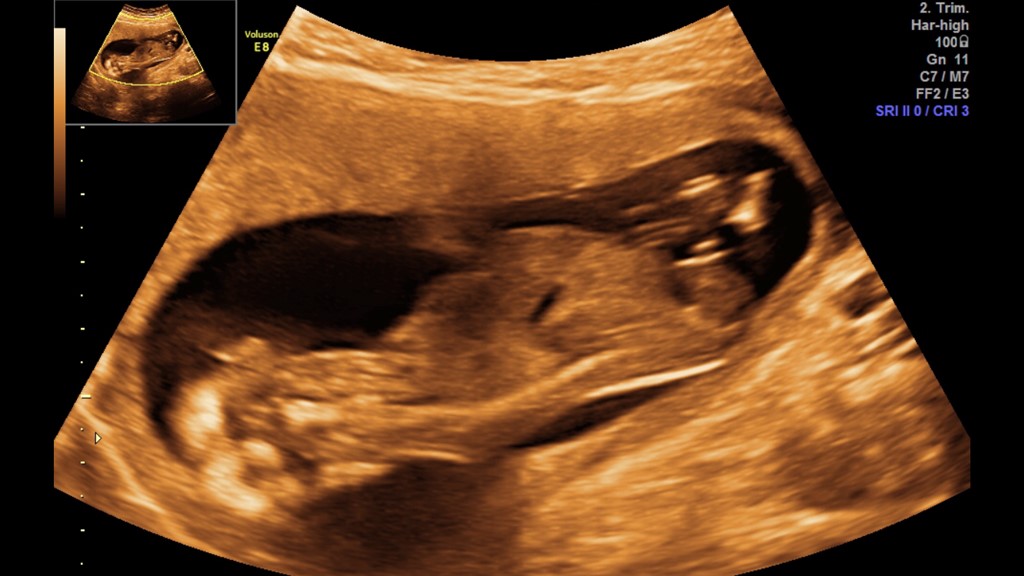

Har kun et billed der er noget værd og som de vurderet ud fra det var en dreng

jeg kan så bare ikk helt forstå hvordan man kan vudere det ud fra det billed og så slet ikk med en navlestreng som sidder i vejen det meste af tiden

Vedhæftede fotos (klik for at se i fuld størrelse)